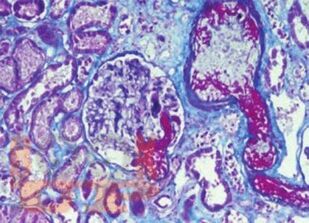

В монографии обобщены результаты исследований авторов и современные литературные данные, посвященные тромботической микроангиопатии у пациентов, находящихся в листе ожидания трансплантации почки, и у реципиентов ренального трансплантата. Большое внимание уделяется патогенетическим механизмам, классификации, проблемам профилактики, ранней диагностики и лечения тромботической микроангиопатии после трансплантации почки, а также влиянию данного осложнения на ближайшие и отдаленные результаты трансплантации.